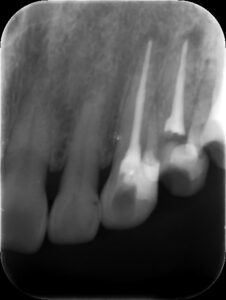

根管充填後レントゲン。歯の痛みや歯茎の腫れが改善したため、バイオセラミックシーラーおよびガッタパーチャにて根管充填を行った。根管治療は2回、2週間で終了。